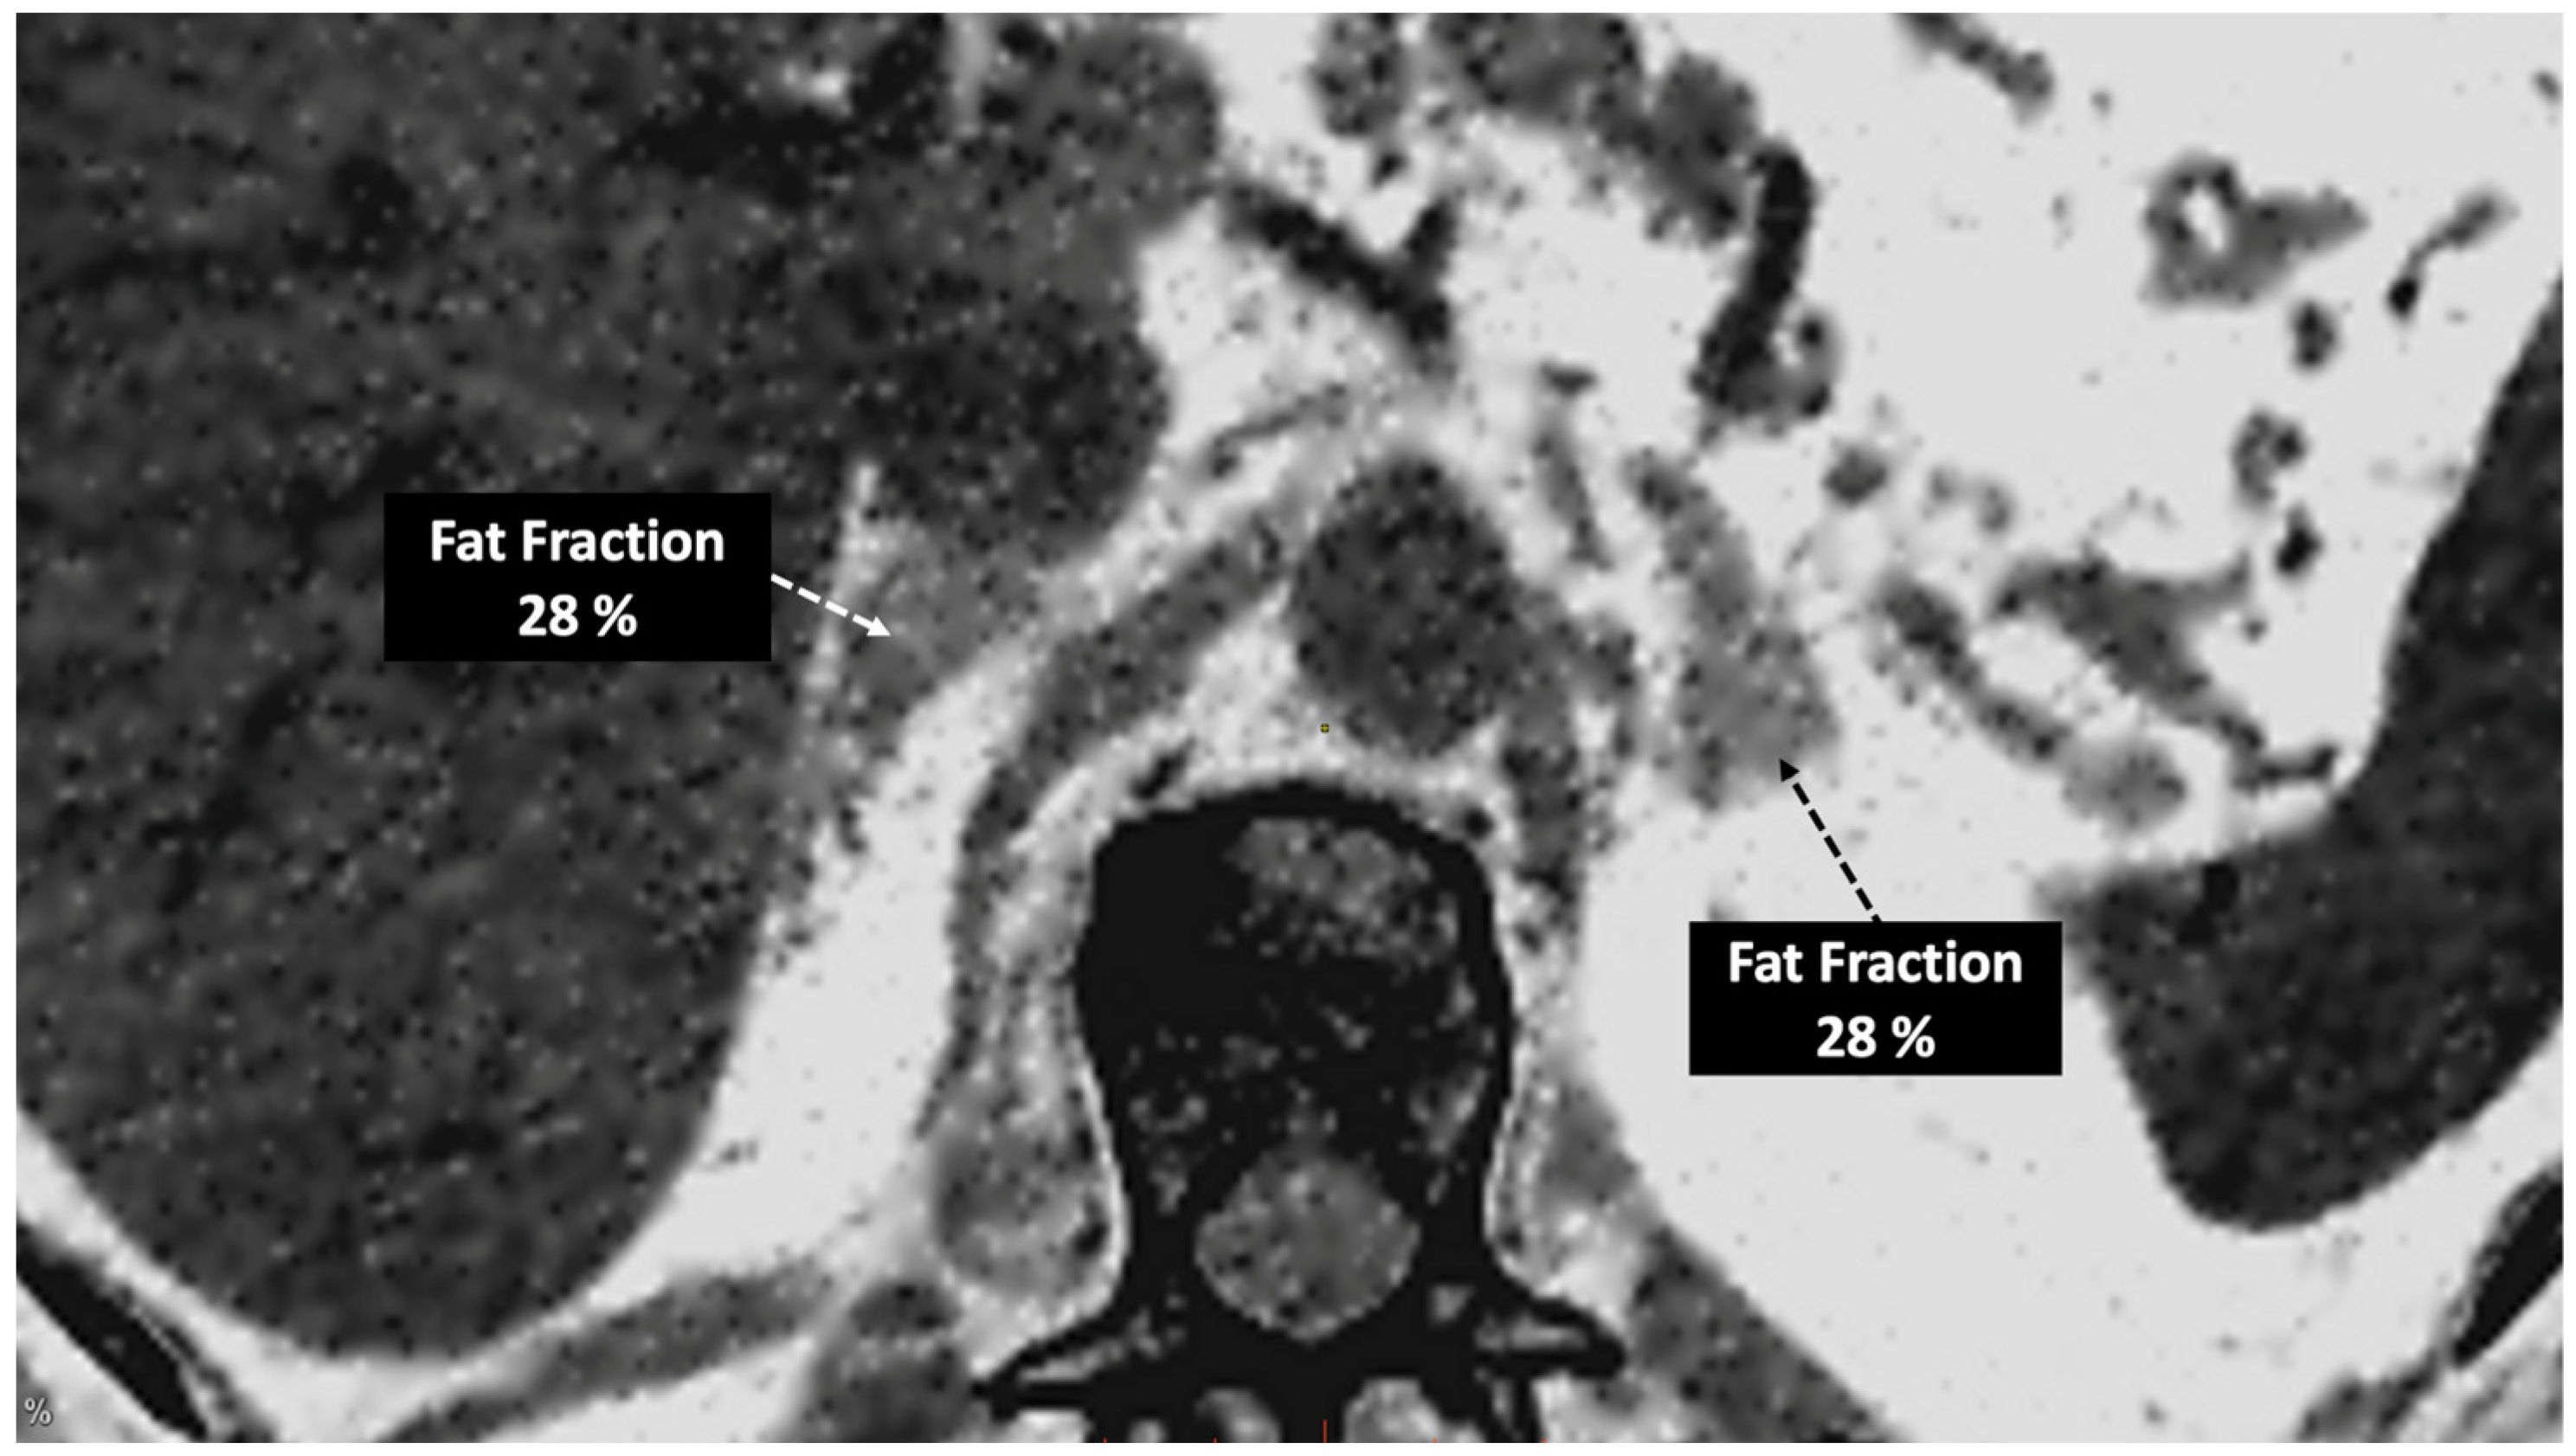

- Imaging of body composition is another growing application of DECT imaging that can be used to improve the evaluation of muscle tissue, visceral adipose tissue (VAT), and subcutaneous adipose tissue (SAT) compartments. SAT and VAT assessment is of special interest in diseases related to metabolic syndrome and critically ill patients [46]. Moreover, sarcopenia is associated with a poorer prognosis in cancer patients [47]. Measuring fat fraction of the skeletal muscle by DECT is a new approach for the determination of muscle quality, an important parameter for the diagnostic confirmation of sarcopenia [48]. In the case of bone mineral density analysis, DECT can provide a more detailed analysis when compared with dual X-ray absorptiometry [49] (Figure 15). Finally, DECT can also be a useful tool for evaluating silicone implants (Figure 16). Silicone contains the heavier element silicon (Z value = 14), whereas soft tissue predominantly comprises lighter elements, depicting the presence of silicone within the soft tissues in cases of silicone gel breast implant rupture and LN silicone spread [50].